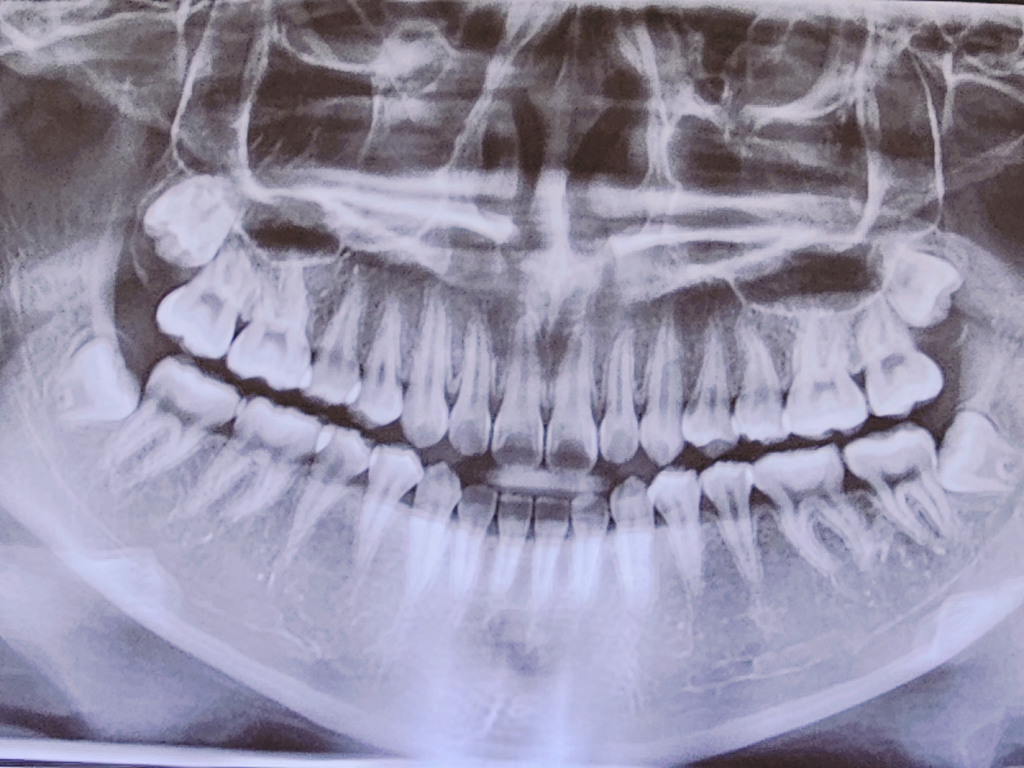

공간이 남아서 의사쌤에게 물어봤더니 자라다가 휘어지게 자랐다고 하는데 진짜 휘어졌나요?

앞니 옆 측절치?랑 아랫니 맞물리는 공간이 넓어서 물어봤더니 휘어졌대요. 교정 하고싶으면 해도 되고 안해도 된다고 하는데

파노라마 방사선 사진만으로 판단하기는 쉽지 않으나 두번째 앞니가 살짝 높이가 안맞고 세번째 치아(송곳니)가 조금 회전된 것 같습니다

기울어져서 맹출한다면 다른 치아들과 높이가 조금 안맞을 수 있고 부분교정으로 다시 원래 각도로 회전시켜 높이를 맞춰줄 수 있습니다 다만 반드시 해줘야 하는 교정은 아닙니다